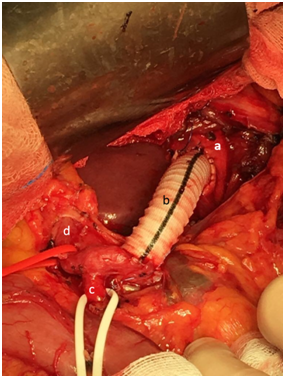

72-year-old male, admitted to the emergency department (ED) for painless obstructive jaundice (total bilirubin of 2,38mg/dL). Emergent ultrasound revealed dilation of the common bile duct (CBD), with 13mm, and of the intra-hepatic ducts, distended gallbladder and no visualization of the distal portion of neither the CBD nor the pancreas (Figure 1).

Figure 1 CBD dilation on ultrasound.